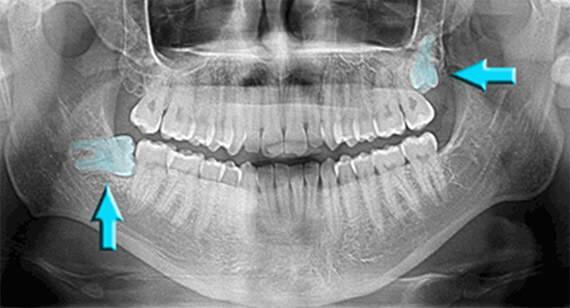

Your last molars, called the third molars or wisdom teeth, typically begin to come in (erupt) during the late teen years or early twenties. When they don’t have room to grow in, or they’re trapped in your jaw because they are tilted or rotated, they are impacted.

You can avoid the pain and possible damaging effects of an impacted wisdom tooth by having it removed early, before its roots are fully developed. We can monitor the development of your wisdom teeth with x-rays, and remove them as soon as we determine they will likely cause difficulties.